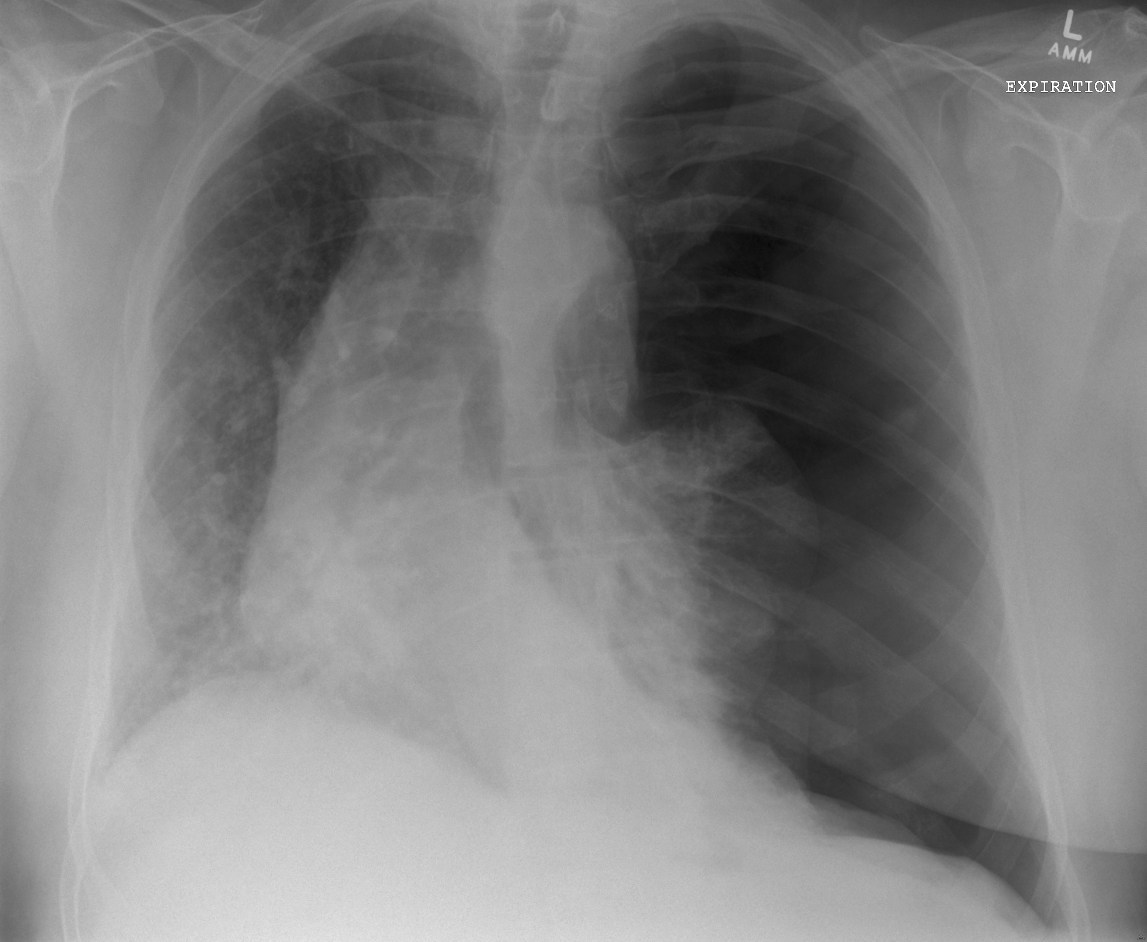

What does this CXR show

tension pneumothorax on the left side